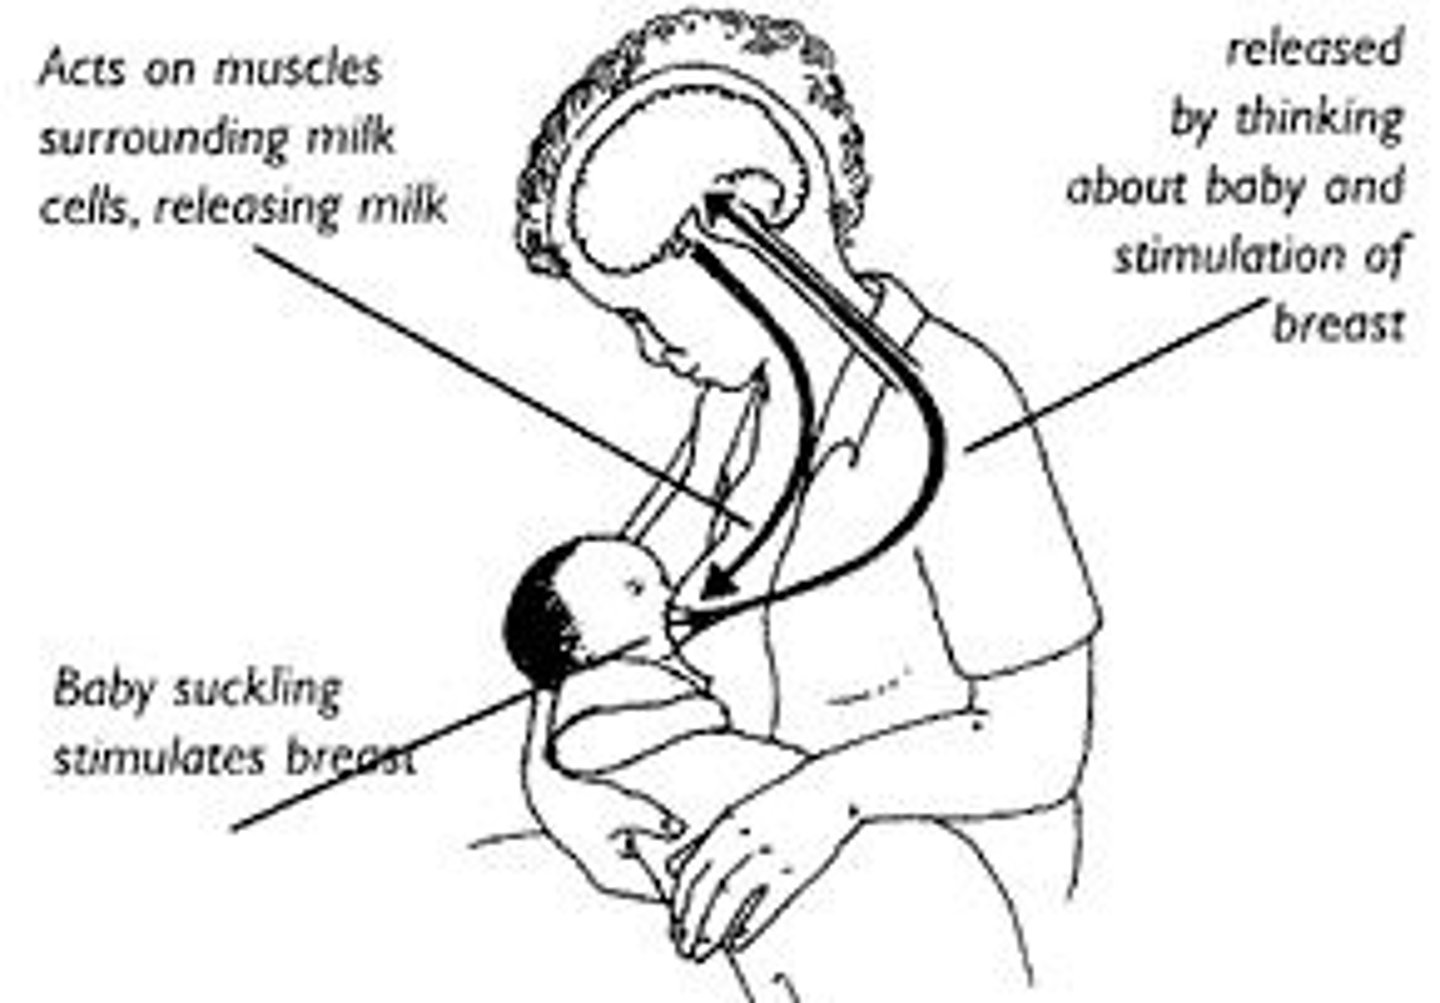

Oxytocin

a hormone released by the pituitary gland that stimulates contraction of the uterus during labor and stimulates lactation after child birth